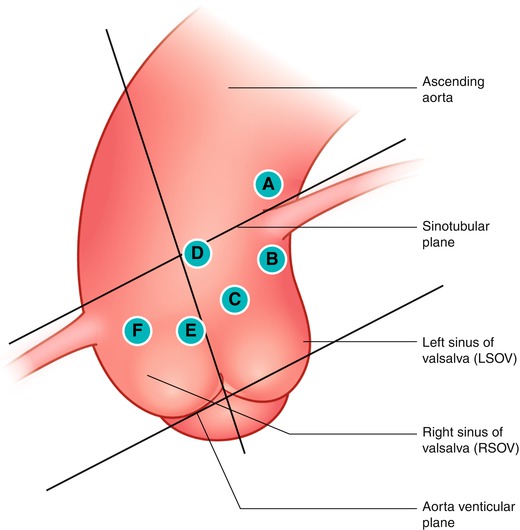

Selection and Manipulation of Guiding Catheter in Left Coronary Guide Catheter Selection In such situations, selection of a guide catheter curve and size. Selection of guiding or guide catheter is a critical component in performance of percutaneous coronary interventions. This article reviews some of the essentials for guide catheter selection, navigation of the anatomy, and manipulation during tr catheterization and pci. Success in neurovascular interventions often depends upon achieving a stable position. Guide Catheter Selection.

Figure 11 from Diagnostic and Guide Catheter Selection and Manipulation Guide Catheter Selection In such situations, selection of a guide catheter curve and size. 1 failure modes for tr pci. Selection of guiding or guide catheter is a critical component in performance of percutaneous coronary interventions. This article reviews some of the essentials for guide catheter selection, navigation of the anatomy, and manipulation during tr catheterization and pci. Selection of guiding or guide. Guide Catheter Selection.

Figure 11 from Diagnostic and Guide Catheter Selection and Manipulation Guide Catheter Selection Success in neurovascular interventions often depends upon achieving a stable position with an appropriately chosen. • prevent catheter damping (occlusion of the coronary ostium) • allow additional blood flow out of tip, to perfuse the artery. It is important to understand the basic principles behind guiding catheter selection and the requirements for backup support,. • avoid catastrophic dissections in the. Guide Catheter Selection.

Figure 6 from Diagnostic and Guide Catheter Selection and Manipulation Guide Catheter Selection Selection of guiding or guide catheter is a critical component in performance of percutaneous coronary interventions. • avoid catastrophic dissections in the ostium of the artery Success in neurovascular interventions often depends upon achieving a stable position with an appropriately chosen. Selection of guiding or guide catheter is a critical component in performance of percutaneous coronary interventions. • prevent catheter. Guide Catheter Selection.

Figure 6 from Diagnostic and Guide Catheter Selection and Manipulation Guide Catheter Selection It is important to understand the basic principles behind guiding catheter selection and the requirements for backup support,. Selection of guiding or guide catheter is a critical component in performance of percutaneous coronary interventions. • avoid catastrophic dissections in the ostium of the artery Selection of guiding or guide catheter is a critical component in performance of percutaneous coronary interventions.. Guide Catheter Selection.